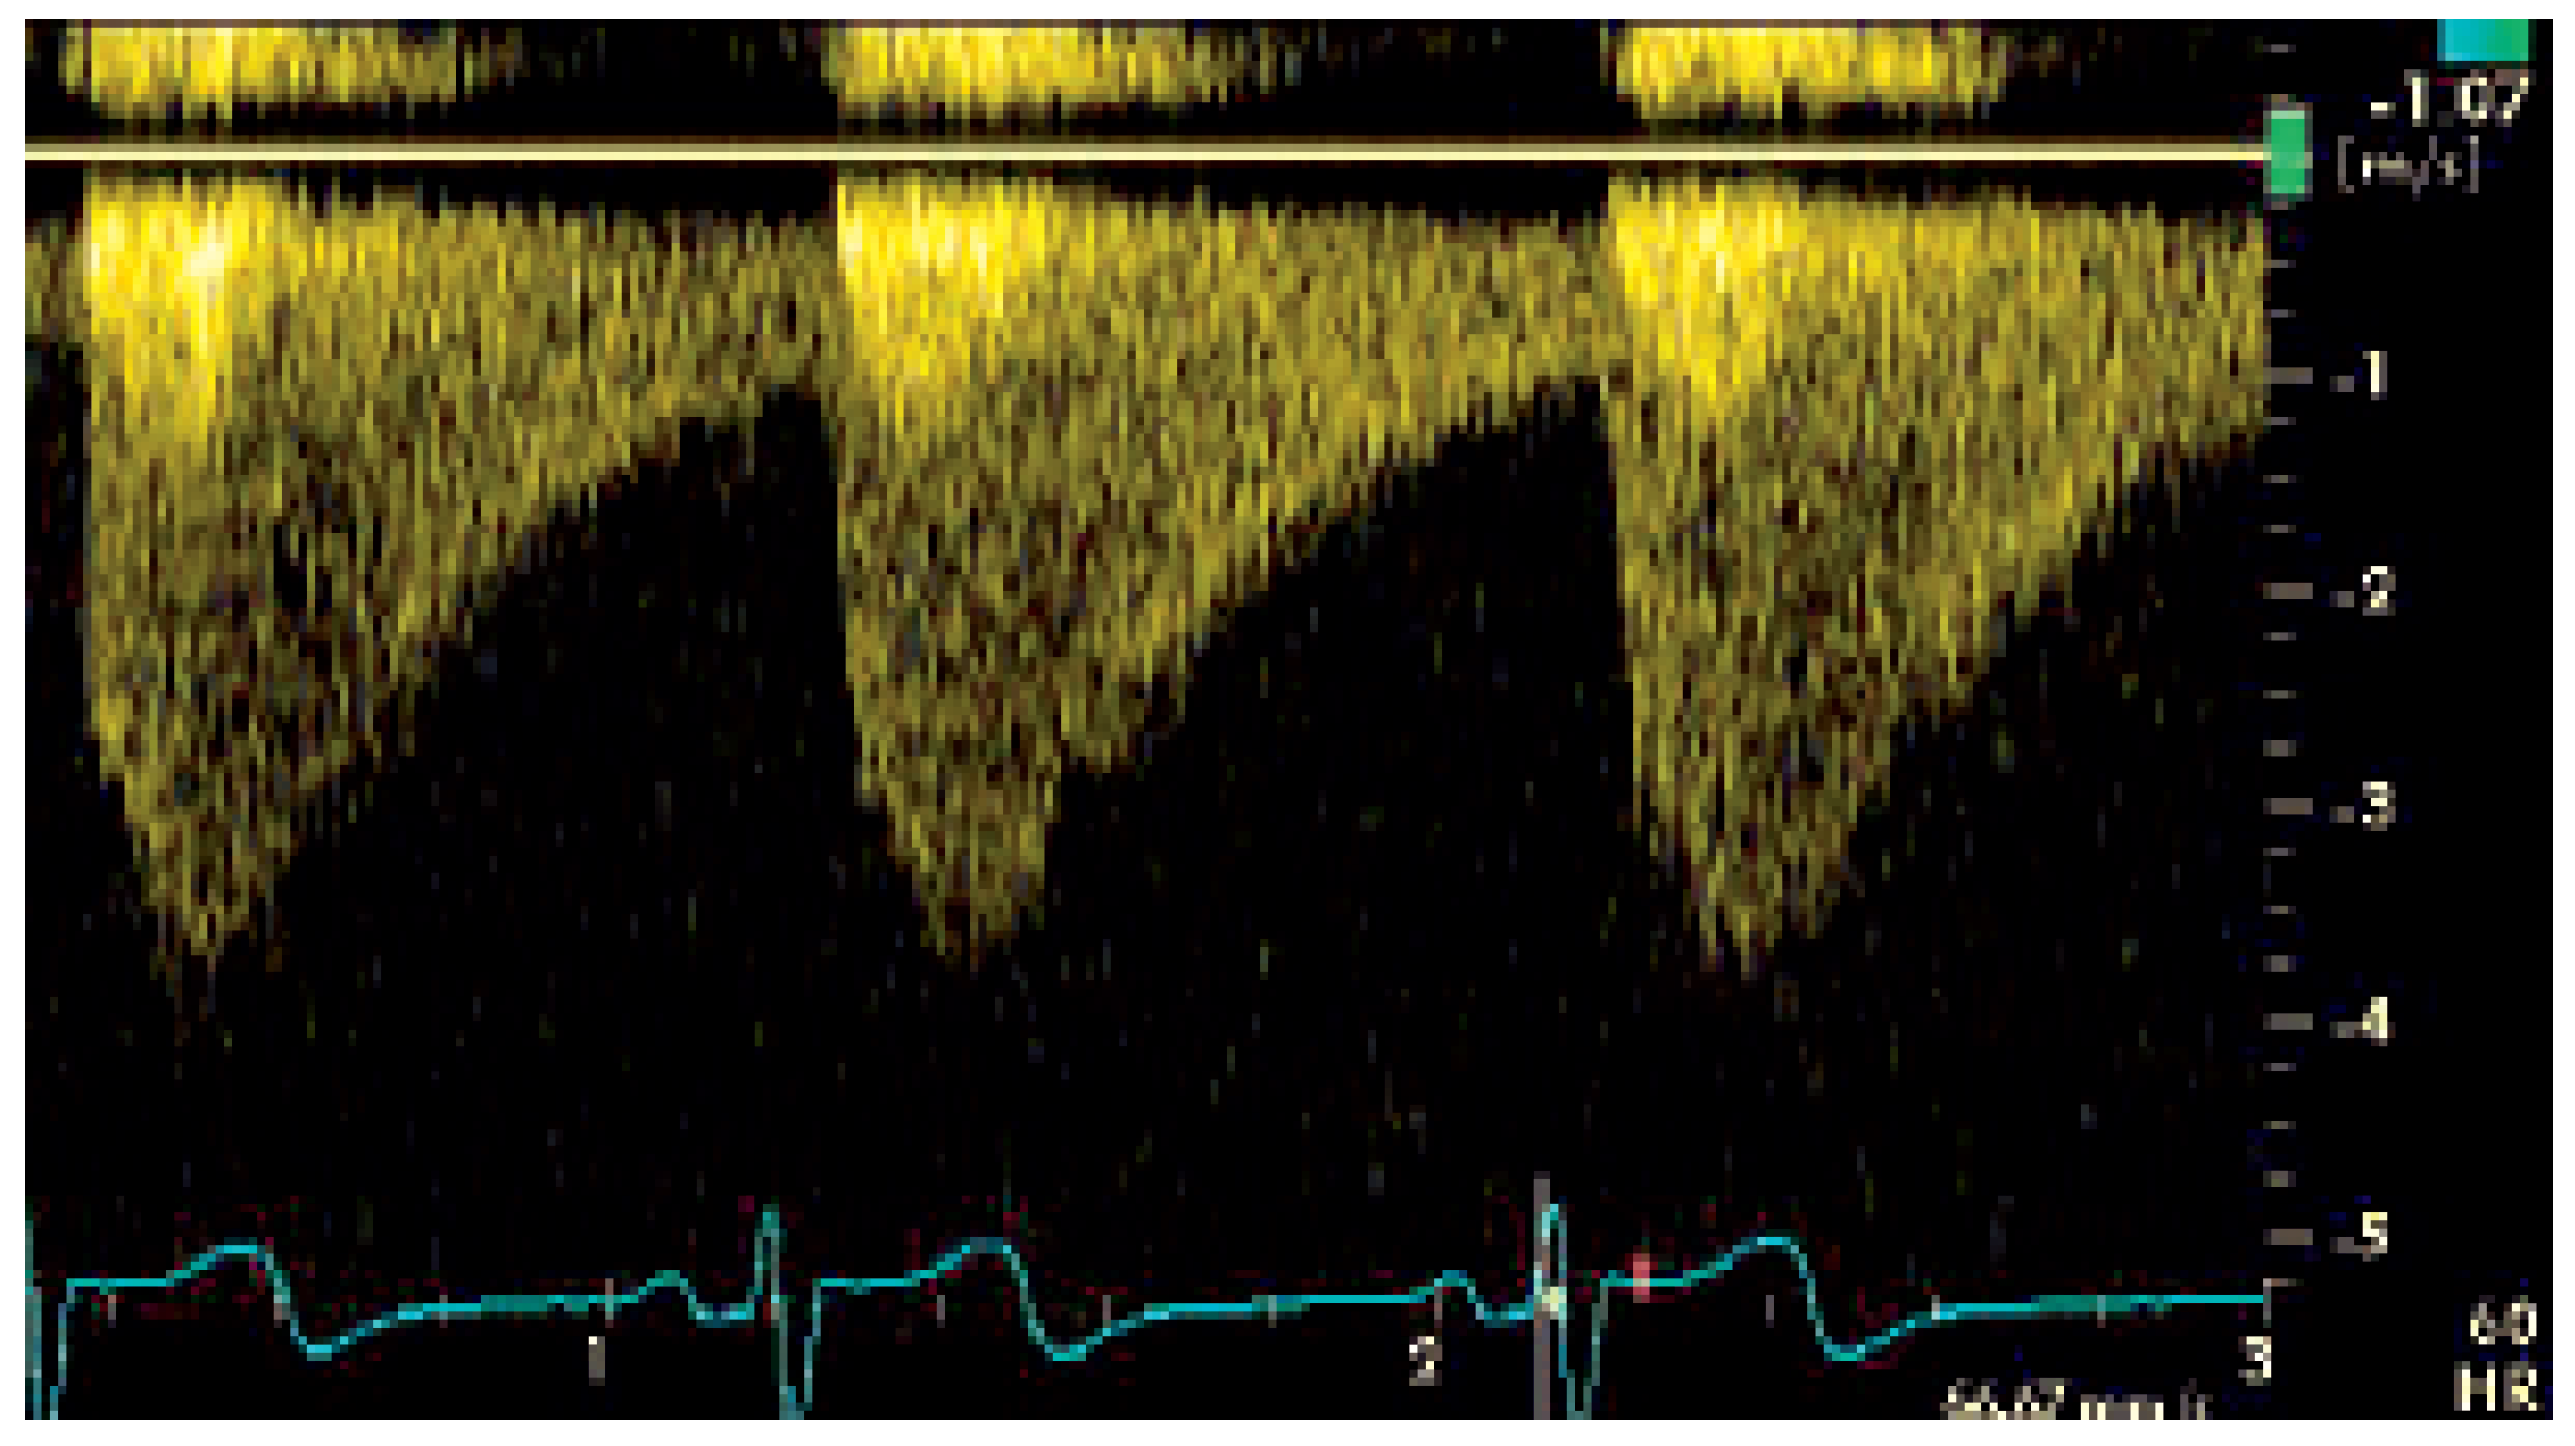

Der hochgradige Verdacht auf eine Aortenisthmusstenose (AIS) wurde durch die MRT bestätigt: hier fand sich eine subatretische, kurzstreckige AIS mit ausgeprägter Kollateralisierung (Figure 2).

Figure 2. Dreidimensionale Rekonstruktion der MR-Angiographie. Eine hochgradige Stenose zeigt sich im Isthmusbereich. Ausgeprägter Umgehungskreislauf durch die Paravertebralarterien und beide Aa. mammariae.